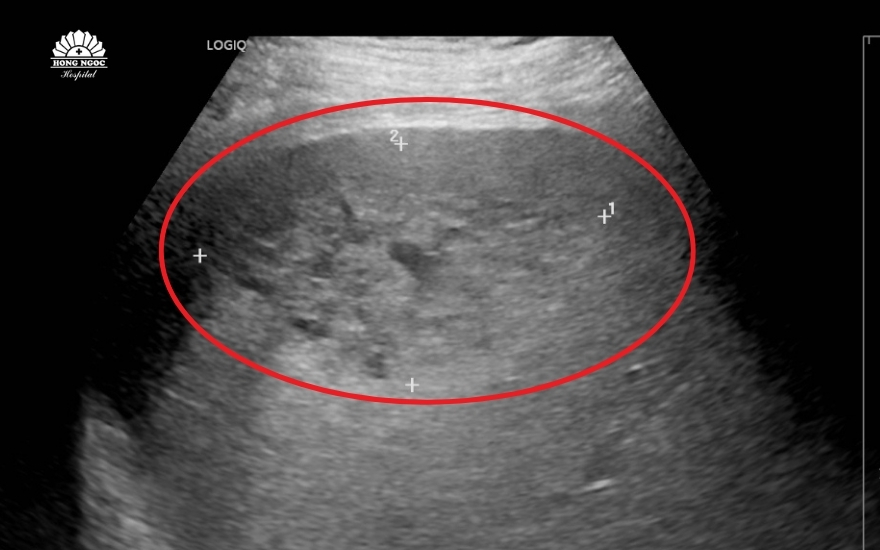

Qua siêu âm ổ bụng, các bác sĩ ghi nhận gan của ông T. to bất thường. Tại thùy gan phải xuất hiện vùng tổn thương lớn sát bao gan, gồm nhiều nang nhỏ kèm viền thâm nhiễm rộng xung quanh. Hai tổn thương chính có kích thước lần lượt 52×88 mm và 25×32 mm. Ngoài ra, bệnh nhân còn có tình trạng dịch ổ bụng và dịch màng phổi.